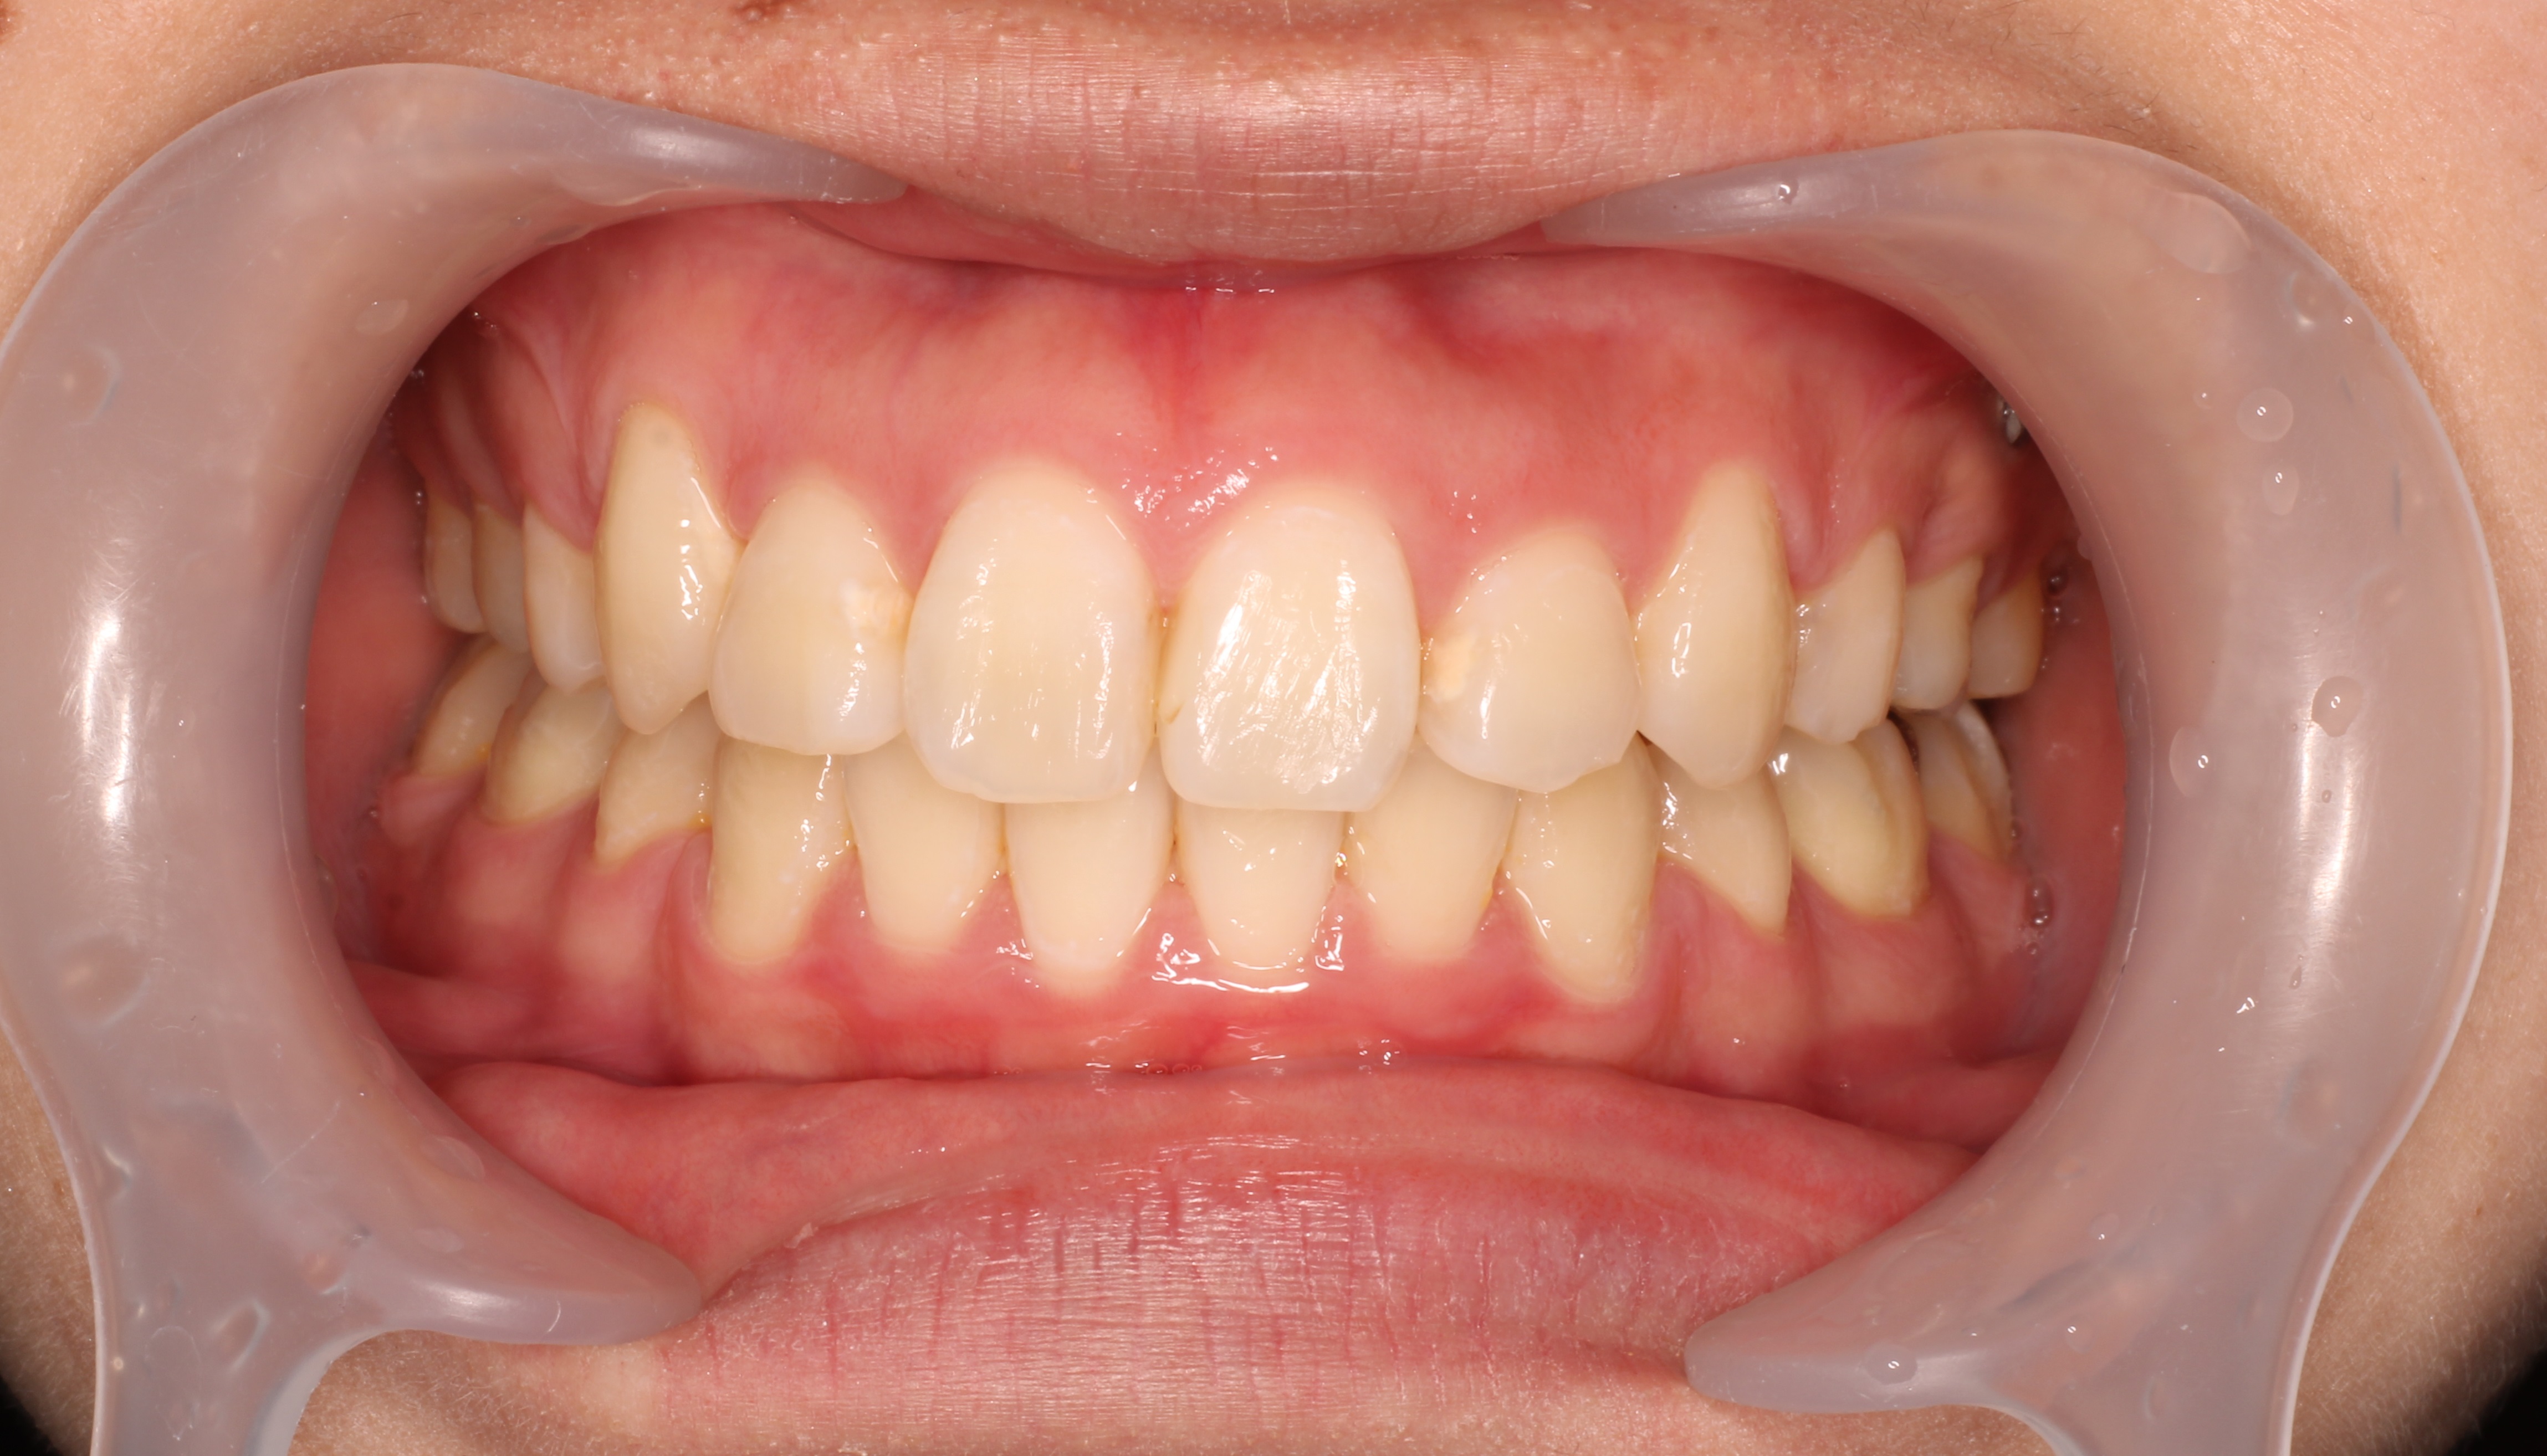

1矯正・マウスピース【治療例1】

治療後